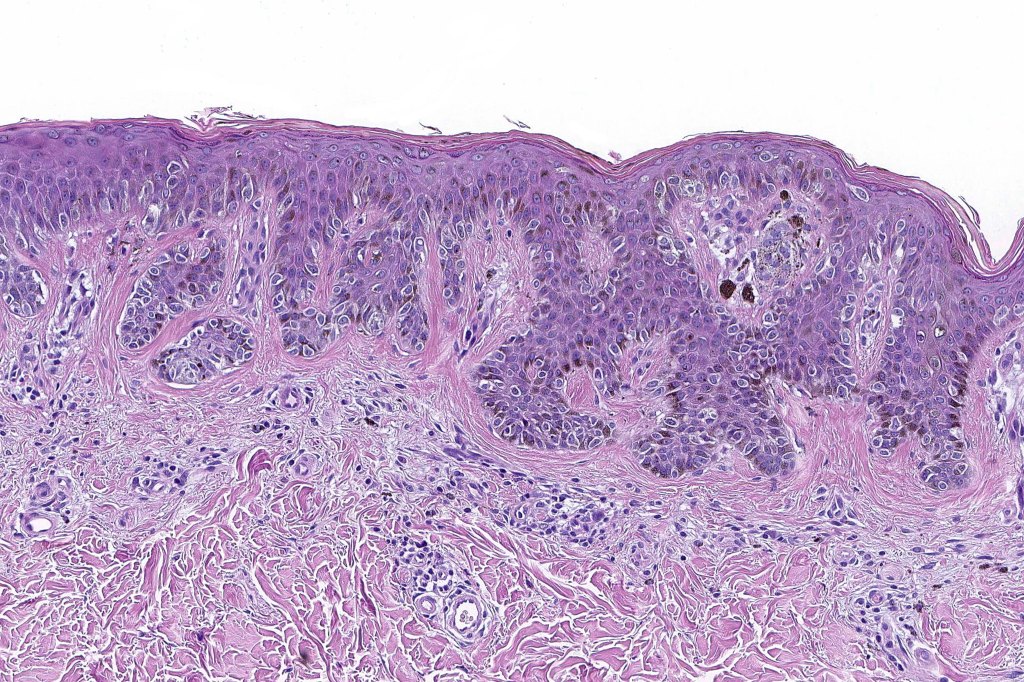

•Architectural disorder- lentiginous and nested, nests abnormally located (at the sides of the rete ridges & overlying the dermal papillae in addition to the tips of the rete ridges rather than solely occupying the tips of the rete ridges as is seen in banal nevi), horizontal orientation & bridging between junctional nests (this should not be confused with bridging between adjacent rete ridge squamous epithelium)

•Host response- eosinophilic & lamellar fibroplasia, increased vascularity, lymphocytic infiltration & pigment incontinence

Dysplastic nevus in the majority of cases is instantly recognizable, often at low power. The most important differential diagnosis is obviously melanoma. In junctional lesions, widespread/uniform high grade atypia, frequent mitoses and Pagetoid spread are indicative of in situ melanoma. In compound lesions, dermal nests larger than junctional ones, expansile dermal nests, severe atypia and mitotic activity indicate the presence of melanoma